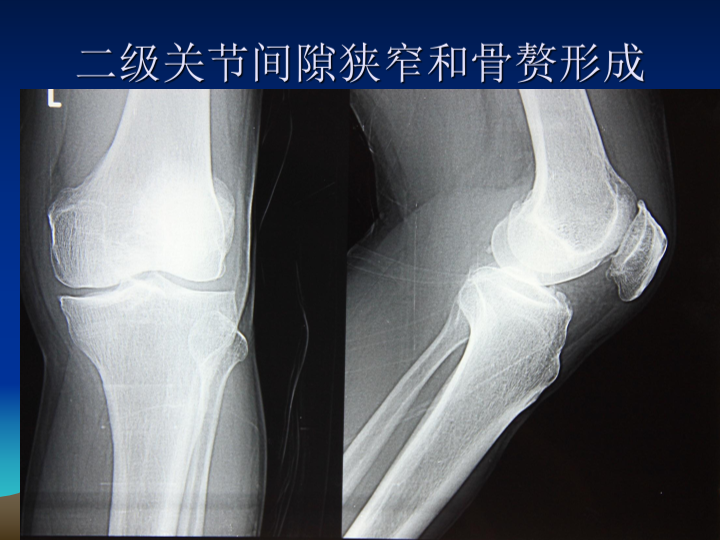

膝关节骨性关节炎阶梯治疗